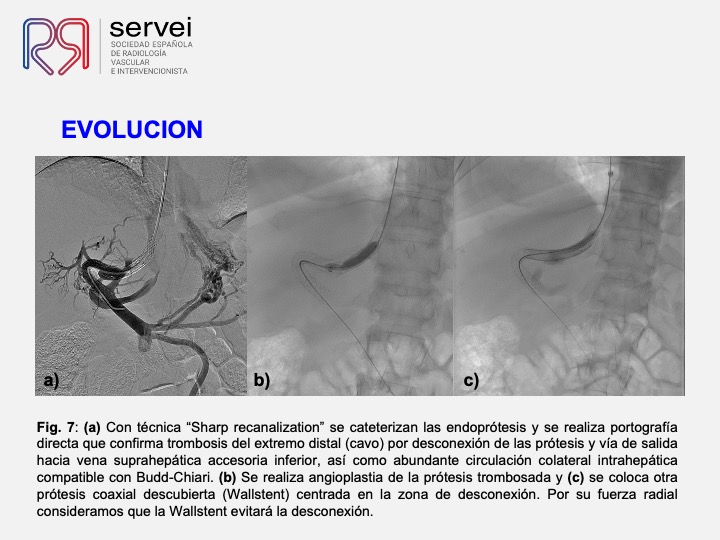

DIPS con técnica de “gun-sight”. Paciente con Síndrome de Budd-Chiari y eventual trombosis protésica